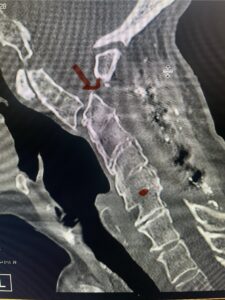

Cervical x-rays revealed a significantly increased atlanto-axial interval (Fig. 5) On review of her imaging studies it was noted that the right C2 isthmus was very thinned by the vertebral foramen (Figs 6a, b, and c) which would make an attempt at placing a C2 pars screw dangerous. A decision was made to perform an occipital-cervical fusion because only possible unilateral fixation and an extensive C1 laminectomy to be performed eliminating a fixation point if a more traditional C1-C2 was performed. Even if C1 lateral mass screws were able to be placed one could only perform a unilateral screw construct fixation to C2. We performed an occipital cervical fusion down to C4 to get enough inferior fixation and C1 laminectomy. The decompression went well. We placed a left unilateral pars screw and bilateral C3 and C4 lateral mass screws. We placed three 12 mm screws in the midline keel (Fig. 7). Postoperatively the patient had all around improvement in her symptoms and did not qualify for rehab. Her post op films at 6 weeks (Fig. 8)

Fig. 6b: Sagittal cervical CT scan demonstrating normal thickness of the left C2 isthmus (red arrow)